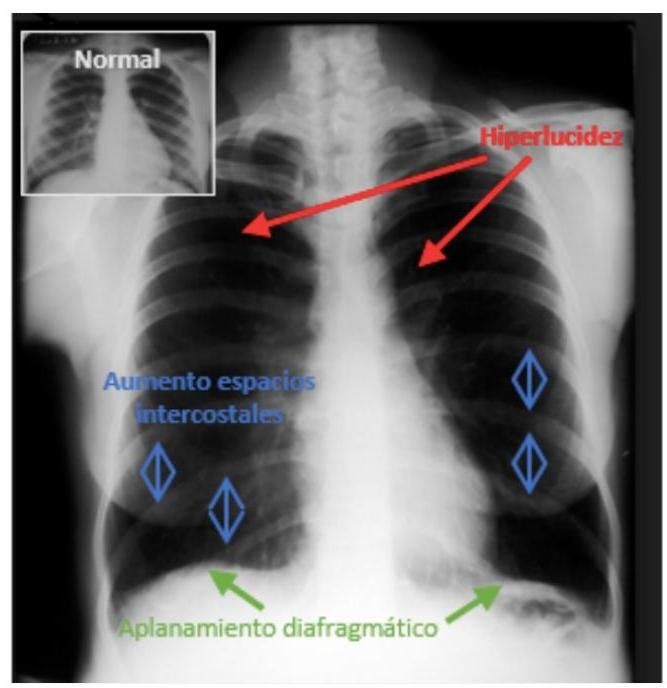

# EPOC ## DEFINICIÓN La **Enfermedad Pulmonar Crónica Obstructiva** es una enfermedad que se caracteriza por una **limitación del flujo aéreo no totalmente reversible** y generalmente **progresiva**, causada por una reacción inflamatoria anormal de los **pulmones** ante **partículas nocivas** y **gases**, fundamentalmente el **humo de tabaco** (o de **leña**). La **limitación al flujo** está producida por una mezcla de **enfermedad de las vías aéreas** (**Bronquiolitis obstructiva**, puesta de manifiesto por una reducción del **Flujo Espiratorio Medio 25-75 %**) y **destrucción parenquimatosa** (**Enfisema**), con una gran variabilidad en cuanto a la contribución de cada una de ellas. La **inflamación crónica** produce **cambios estructurales** y **estrechamiento de las vías pequeñas**. La **destrucción del parénquima pulmonar**, también de origen inflamatorio, conduce a la ruptura de las uniones entre los **alvéolos** y las pequeñas vías aéreas y a una disminución de la **retracción elástica del pulmón**. Estos cambios afectan a la capacidad de las vías aéreas de permanecer abiertas durante la espiración. **ENFISEMA**: dilatación del **acino** (vía aérea distal a un **bronquiolo terminal**) y **destrucción de la pared alveolar**. Es un concepto **anatomopatológico**, erróneamente usado en forma clínica. **BRONQUITIS CRÓNICA**: definida por la presencia de **tos** y **expectoración** durante al menos **3 MESES AL AÑO**, durante **2 años consecutivos**. Sí es un **concepto clínico**, pero no refleja la importancia en la **limitación del flujo aéreo** en la EPOC.  # FISIOPATOLOGÍA El **proceso inflamatorio** que ocurre en la EPOC es una ampliación de la **respuesta inflamatoria** que tiene lugar en el aparato respiratorio normal ante la agresión de **irritantes crónicos** como el **humo de tabaco** o **leña**. Su patrón **inflamatorio** incluye a **Neutrófilos**, **Macrófagos** y **Linfocitos** (fundamentalmente **CD8**). Estas células liberan **mediadores inflamatorios** que atraen **células inflamatorias** desde la circulación, amplifican el **proceso inflamatorio** e inducen **cambios estructurales** que pueden producir **fibrosis en vías pequeñas**. El proceso es amplificado por el **estrés oxidativo** y el exceso de **proteinasas** en el pulmón. ## CAMBIOS ESTRUCTURALES | **VÍAS AÉREAS PROXIMALES** (>2 mm de diámetro) | Aumento de las **células caliciformes**, **hipertrofia de las glándulas de la submucosa** y **metaplasia escamosa**. | | :--: | :-- | | **VÍAS AÉREAS DISTALES** (<2 mm de diámetro) | **Engrosamiento de la pared**, **fibrosis peribronquiolar**, **exudado inflamatorio endoluminal** y **disminución del calibre de las vías aéreas** (**bronquiolitis obstructiva**). | | **PARÉNQUIMA PULMONAR** (**bronquiolos respiratorios** y **alvéolos**) | **Destrucción de la pared alveolar** y **apoptosis de células epiteliales y endoteliales**. **Enfisema centroacinar** o **centrolobulillar** (**dilatación y destrucción de bronquiolos respiratorios**): común en fumadores y predomina en campos superiores. **Enfisema panacinar** o **panlobulillar** (**destrucción de los sacos alveolares y bronquiolos**): en déficit de **alfa-1 antitripsina** y predomina en campos inferiores. | | **VASOS SANGUÍNEOS PULMONARES** | **Engrosamiento de la íntima**, **disfunción endotelial** y **aumento de la capa muscular**; conduce a **Hipertensión Pulmonar**. | ## LIMITACIÓN DEL FLUJO AÉREO Y ATRAPAMIENTO AÉREO La **inflamación**, **fibrosis** y **exudados endoluminales** en las pequeñas vías causan reducción del **FEV1** y de la relación **FEV1/FVC**. Producen además un **atrapamiento aéreo** durante la espiración con **hiperinsuflación**. Esto reduce la **capacidad inspiratoria**, de forma que aumenta la **capacidad residual funcional**, sobre todo durante el **ejercicio**. ## ALTERACIONES EN EL INTERCAMBIO DE GASES  Son secundarias al **enfisema**, **alteraciones en la relación V/Q** por **obstrucción de las vías aéreas periféricas** y **función muscular alterada**. Causa de **hipoxemia** e **hipercapnia**. ## HIPERTENSIÓN PULMONAR Es una **complicación tardía** de la EPOC. Su causa es la **vasoconstricción pulmonar hipóxica** de las arterias pulmonares de pequeño calibre, sumado a **hiperplasia de la íntima** e **hipertrofia muscular**. Puede conducir a **hipertrofia ventricular derecha** e incluso a **insuficiencia cardiaca derecha** (**cor pulmonale**). # EPIDEMIOLOGÍA - Aumenta su **incidencia** en los últimos años, relacionado al **consumo de tabaco**. - El **humo de tabaco** es el principal **desencadenante** de la EPOC. - **Tasa de mortalidad**: hombres 19.8 % y mujeres 16.7 % (también ha aumentado). - **Morbilidad alta**; se registran múltiples recursos para atención en diferentes niveles. - Promedio de **estancia hospitalaria** de 9 días. ## FACTORES DE RIESGO | **Tabaquismo** (**humo de tabaco**) | **Tasa de disminución anual del FEV1**. La **suspensión del tabaco** no lleva consigo **recuperación de función pulmonar**, pero se **enlentece la caída anual del FEV1**. | | :-- | :-- | | **Ocupaciones** | **Humos industriales** y **polvos minerales**. | | **Biomasa** | Empleo de **carburantes de origen orgánico** para cocinar (**humo de leña**). | | **Genética** | Deficiencia de **Alfa-1 Antitripsina** (menos del 1 % de los casos). Provoca **enfisema precoz** (antes de los 45 años). | | **Contaminación** | Los **contaminantes ambientales urbanos** son perjudiciales. La **incidencia** y **mortalidad de bronquitis y enfisema** son mayores en **áreas industrializadas**. | ## CLÍNICA - **Disnea al ejercicio** (el síntoma más importante en la EPOC); aparece en la **sexta década** de la vida y es progresiva. - **Tos crónica**. - **Producción regular de esputo**. - **Bronquitis frecuente** en invierno. - **Sibilancias**. Es común evidenciar **historia de tabaquismo** de por lo menos 20 cigarrillos diarios durante al menos 20 años. ## EVALUACIÓN DE LA DISNEA: ESCALA DEL MEDICAL RESEARCH COUNCIL ## SÍNDROME DE SUPERPOSICIÓN (OVERLAP/SOLAPAMIENTO) Asociación de dos **Síndromes Respiratorios**. Lo más común es **EPOC + SAOS**. Estos pacientes desarrollan **hipertensión pulmonar**, **cor pulmonale**, **poliglobulia** y **alteraciones diurnas de los gases arteriales** de manera más precoz y grave que los **pacientes** con EPOC aislada. # DIAGNÓSTICO ## ESPIROMETRÍA Es imprescindible para establecer el **diagnóstico** al demostrar **limitación del flujo aéreo** con **reversibilidad parcial y no completa**. Debe realizarse en todo paciente con sospecha de cuadro clínico de EPOC. Se establece con lo siguiente: 1. El **FEV1** está por debajo del 80 % del predicho. 2. Relación **FEV1/FVC** menor a 0.7. | | **OBSTRUCTIVO** | **RESTRICTIVO** | **MIXTO** | | :--: | :--: | :--: | :--: | | FVC % | Normal | ↓ | ↓ | | FEV1 % | ↓ | ↓ | ↓ | | FEV1/FVC | ↓ | Normal | ↓ | - **PATRÓN OBSTRUCTIVO**. ## CRITERIOS DE GOLD (Global Initiative for Lung Disease) Se establece en la medición del **FEV1 posbroncodilatador**, además de la presencia de síntomas como **atrapamiento aéreo**, **insuficiencia respiratoria**, **afectación sistémica** y **comorbilidad asociada**. | **ESTADIOS** | **FEV1** (% sobre el teórico o predicho) | Relación **FEV1/FVC** | | :--: | :--: | :--: | | **ESTADIO I (LEVE)** | >80 % | | | **ESTADIO II (MODERADA)** | 80 %-50 % | Menor a 0.7 | | **ESTADIO III (GRAVE)** | 50 %-30 % | | | **ESTADIO IV (MUY GRAVE)** | <30 % (menos del 30 % define EPOC muy grave) | | A partir del **GOLD III** se indica **oxígeno suplementario continuo**. ## GASOMETRÍA ARTERIAL - **INSUFICIENCIA RESPIRATORIA**: solo se establece a través de una **Gasometría de Sangre Arterial**. - Necesaria para determinar la **gravedad de la insuficiencia** e indicar **oxígeno suplementario en el domicilio**. - En la mayoría de los casos, no proporciona datos para el diagnóstico de EPOC. - Sin embargo, se debe realizar en todos los **pacientes con EPOC** para identificar comorbilidades y excluir otras patologías.  # TOMOGRAFÍA No es de rutina, pero puede usarse para síntomas que no concuerden con hallazgos en la **espirometría**, **anormalidades en la Rx de Tórax** o pacientes en protocolo de **cirugía pulmonar** (**resección de bulas**, **reducción de volumen**). ## ECOGRAFÍA - Útil para el **diagnóstico de Hipertensión Arterial Pulmonar (HAP)**. - Realizarse en casos específicos de EPOC, para determinar el grado de HAP cuando no hay relación con el grado de avance de la **enfermedad**. Otros: Determinación de **Alfa-1 Antitripsina**, **gammagrafía ventilación-perfusión**, **citología de esputo**. # TRATAMIENTO ## FARMACOLÓGICO ## **Primera elección: BRONCODILATADORES (agonistas beta-2) DE ACCIÓN CORTA - SALBUTAMOL** - La **terapia inhalatoria** es la **vía de elección** por el tiempo de acción, menor dosis y menos **efectos colaterales**. - Favorecen el incremento de la **capacidad al ejercicio** sin que haya modificación del **FEV1**. **PERSISTENCIA DE SÍNTOMAS**: agregar **Anticolinérgico de Acción Corta** o **Broncodilatador de acción prolongada**. - El **bromuro de Tiotropio** se emplea en una sola dosis diaria, con lo que se mantienen adecuados niveles del medicamento y se favorece la reducción de las **exacerbaciones de la EPOC**. ## **EPOC MODERADO-GRAVE** con **exacerbaciones frecuentes** **Primera elección**: **Broncodilatadores de Acción Corta** + **Broncodilatadores de Acción Larga** (**agonistas beta-2** o **Anticolinérgicos**). - Los **glucocorticoides inhalados** **están indicados** en pacientes con buena respuesta. - Usar **glucocorticoides orales a largo plazo** produce **miopatía** y **debilidad muscular**. | **Agonistas beta-2 de Acción Corta** | **Agonistas beta-2 de Acción Prolongada** | **Anticolinérgicos de Acción Corta** | **Anticolinérgicos de Acción Prolongada** | | :--: | :--: | :--: | :--: | | Salbutamol, Terbutalina | Salmeterol, Formoterol | Bromuro de Ipratropio | Bromuro de Tiotropio (dura 24 horas) | ## METILXANTINAS DE ACCIÓN PROLONGADA - Pueden ser usadas con previa **determinación del medicamento en plasma**. - Indicadas en quienes la **terapia convencional** no ha funcionado o por **incapacidad para la terapia inhalatoria** (**Teofilina**). **INHIBIDOR DE LA FOSFODIESTERASA 4**: el **Roflumilast** mejora la función pulmonar y los síntomas de EPOC. ## COMBINACIONES EFECTIVAS a) **SALMETEROL/FLUTICASONA** b) **FORMOTEROL/BUDESONIDA** Los **medicamentos combinados** deben suspenderse después de 4 semanas si no hay beneficio. ## VACUNAS Aplicar las siguientes **vacunas** a **TODOS** los enfermos de EPOC, para reducir la **MORTALIDAD** (reducción de **hospitalizaciones** y **muertes**). - **Vacuna Antigripal** - **Vacuna Antineumocócica** (al menos una vez en la vida) ## Terapias que NO SE DEBEN USAR: - **Antibióticos profilácticos**. - **Antitusígenos** (síntoma molesto, pero es un **mecanismo de defensa** importante para los pacientes con **EPOC**). - **Mucolíticos** (no han mostrado eficacia). - **Inmunomoduladores** (no se recomiendan porque requieren más evidencia científica para conocer su efectividad). # NO FARMACOLÓGICO ## OXÍGENO SUPLEMENTARIO **OBJETIVO**: mantener **PaO2** en reposo >60 mmHg. - Su empleo **AUMENTA LA SUPERVIVENCIA**, el sueño y la capacidad intelectual en **EPOC estadio IV**. - Se debe indicar a **largo plazo** por **más de 15 horas al día** para prevenir la **Hipertensión Arterial Pulmonar**. - Iniciar a partir de **GOLD III**. **OXÍGENO A DOMICILIO** a) **PaO2** <55 mmHg b) **SpO2** <88 % - Se puede utilizar aunque no cumpla lo anterior, si presenta **desaturación durante el ejercicio** o **durante el sueño**. - Si la **PaO2** está entre 56-60 mmHg o la **SpO2** ≥88 %, emplear oxígeno cuando haya **poliglobulia** (**Hematocrito (Hcto.)** >55 %), **cor pulmonale** o **Hipertensión Arterial Pulmonar**. ## VENTILACIÓN MECÁNICA NO INVASIVA - Disminuye la retención de **dióxido de carbono**. - Indicada en casos seleccionados de **EPOC estadio IV**. - **Hipercapnia**: combinar **VMNI** con **Oxígeno a largo plazo**. ## BULECTOMÍA - La **descompresión pulmonar** por medio de **resección de una bula gigante** mejora la función respiratoria. - Indicada en **Enfisema Pulmonar heterogéneo**, con **predominio en lóbulos superiores** y si la **rehabilitación** no ha mejorado la **capacidad de realizar el ejercicio**. ## ABANDONO DEL TABACO - Es la **medida más importante y eficaz** para tratar la EPOC. - Aumenta la **supervivencia**. ## REHABILITACIÓN - Mejora la **tolerancia al ejercicio** y la **calidad de vida**. Debe incluir **consejería nutricional**. - No ha demostrado impacto en la **supervivencia**. # EXACERBACIONES DE EPOC Son extraordinariamente importantes y deben registrarse como parte de la **historia clínica (HC)**. Se **definen** como un **empeoramiento agudo de los síntomas respiratorios** que necesitan una **terapia adicional**. Debe evaluarse inicialmente la **gravedad de la reagudización** (en función de la **comorbilidad**, **estadio** y **antecedentes de reagudizaciones**) para decidir el **manejo ambulatorio**, **hospitalario** o en **UCI**. ## ETIOLOGÍA **La causa más común** de las exacerbaciones es la **infección** y la **contaminación ambiental**; en una tercera parte de las exacerbaciones graves no se identifica el origen. ## 1. **BACTERIANA** 75 % ## 2. **VIRAL** 25 % - ***H. influenzae*** (el más frecuente si no hay **vacuna**).*** - ***S. pneumoniae*** - ***M. catarrhalis*** ## TRATAMIENTO ## CLASIFICACIÓN DE ANTHONISEN | **TIPO I (Severo)** | Presencia de los 3 criterios | **Antibiótico** y **Hospitalización** | | :-- | :-- | :-- | | **TIPO II (Moderado)** | Presencia de 2 criterios | **Antibiótico** y, si ha tenido **purulencia**, hospitalizar. | | **TIPO III (Leve)** | Presencia de 1 criterio | No requiere **antibiótico**. Manejo ambulatorio. | 1. Incremento de la **disnea**. 2. Incremento del **volumen del esputo**. 3. Incremento de la **purulencia del esputo**. **Primera elección**: **Agonistas beta-2 inhalados** (con o sin **anticolinérgicos**) y **glucocorticoides sistémicos**. - **Prednisolona** 30-40 mg al día durante 7-10 días. ## ANTIBIÓTICOS - Duración: 3-10 días. | **CONDICIÓN** | **ANTIBIÓTICO** | | :-- | :-- | | No ha recibido antibiótico en las últimas 6 semanas.<br>Menos de 4 exacerbaciones al año. | a) Amoxicilina<br>b) Doxiciclina<br>c) TMP/SMX | | Uso de antibiótico en las últimas 6 semanas.<br>Más de 4 exacerbaciones al año o fracaso del tratamiento mencionado anteriormente. | a) Cefuroxima<br>b) Amoxicilina/Clavulanato<br>c) Azitromicina (alergia a betalactámicos)<br>d) Claritromicina (alergia a betalactámicos) | | **Exacerbación grave** de **EPOC Grave o MUY Grave**.<br>Fracaso del tratamiento anterior. | a) Levofloxacino<br>b) Moxifloxacino<br>c) Gatifloxacino | La **VMNI** mejora el equilibrio ácido-base, la **frecuencia respiratoria (FR)** y la **disnea**; disminuye la estancia hospitalaria y la **necesidad** de intubación. **INTUBACIÓN**: **acidosis respiratoria grave** (pH <7.20-7.25), **bajo nivel de conciencia**. La **Hospitalización a Domicilio** ("Hospital en Casa") y los esquemas de **Alta Precoz Asistida** son seguros y efectivos como alternativa para las exacerbaciones en casos de **requerir** hospitalización. # PRONÓSTICO La **edad** y el valor del **FEV1** al momento del **diagnóstico** son los mejores criterios para predecir la **supervivencia**. ## MORTALIDAD - El **ritmo de disminución anual del FEV1** parece ser el índice que mejor se relaciona con la **mortalidad**. - La **mortalidad** aumenta respecto a la de la población general cuando el **FEV1** es menor al 50 %. - Un **IMC** < 21 se asocia a aumento de la **mortalidad**. - Otros factores: **edad avanzada**, **hipoxemia grave**, **magnitud de la hipertensión pulmonar**, **hipercapnia**, **comorbilidades**. El **FACTOR QUE MÁS INCIDE EN LA EVOLUCIÓN** es la persistencia del **TABAQUISMO**. # ALGORITMO DE TRATAMIENTO